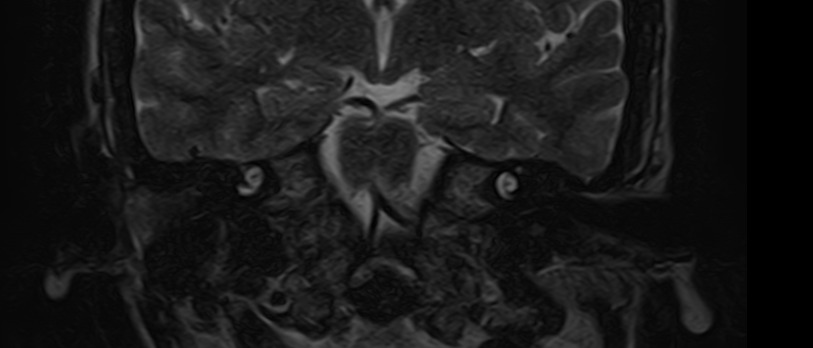

Внутреннее ухо – важная часть слуховой и вестибулярной систем тела человека, находящаяся в толще пирамиды височной кости.

Внутреннее ухо содержит слуховой орган (улитку) и орган равновесия (преддверие и полукружные каналы), патологические изменения которых в свою очередь приводят к развитию нейросенсорной тугоухости и вестибулярных нарушений.